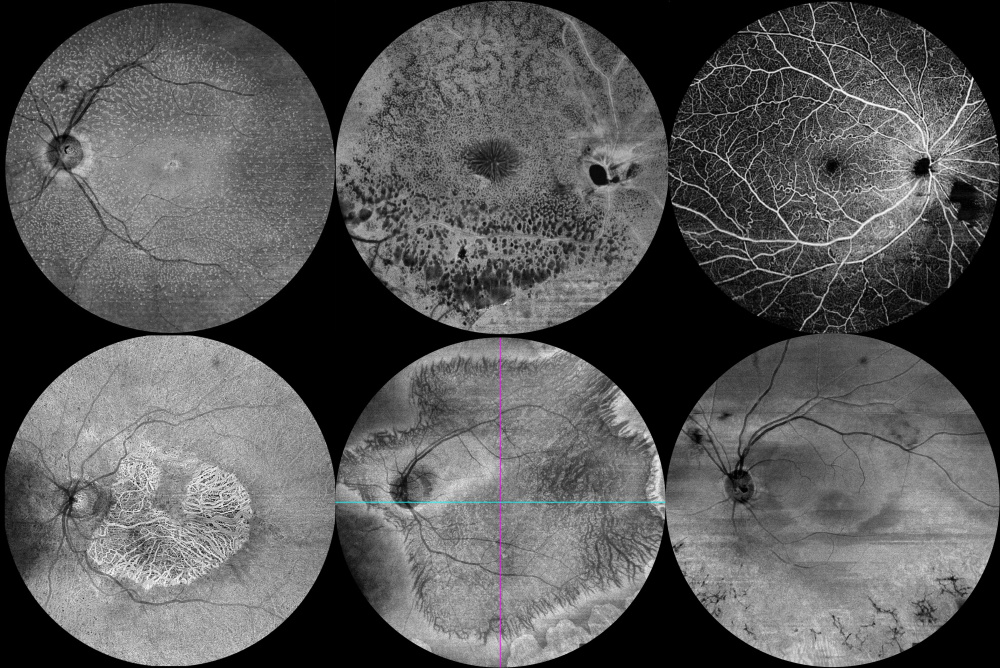

Título: En face signatures of retinal inheritance

Autor: Mariana Francisco

Coautores: Sílvia Simão, João Pedro Marques

Instituição: Unidade Local de Saúde de Coimbra

Descrição: These images illustrate a spectrum of inherited retinal diseases (IRD) captured with en face optical coherence tomography (OCT) and optical coherence tomography angiography (OCT-A). Top row, left to right: fundus albipunctatus (RDH5), X-linked retinoschisis (RS1), and familial retinal arteriolar tortuosity (COL4A1). Bottom row, left to right: maternally inherited diabetes and deafness (MT-TL1), gyrate atrophy of the choroid and retina (OAT), and sector retinitis pigmentosa (RHO).